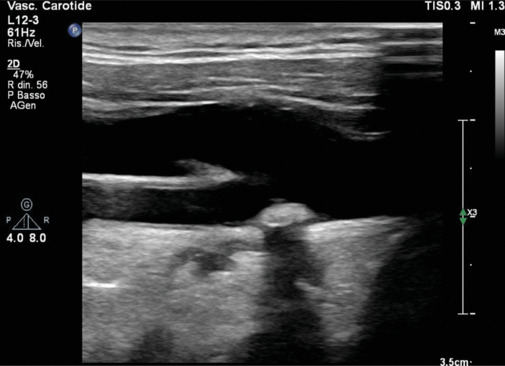

心血管疾病(cvd)仍然是世界范围内发病率和死亡率的主要原因,传统的预防措施侧重于改变生活方式、药物干预和风险分层。最近,成像已经成为心血管预防的一种有趣的工具。这篇综述探讨了各种成像方式在早期发现、风险评估和疾病监测中的作用。无创技术,如颈动脉超声、动脉硬度评估、超声心动图和冠状动脉钙评分,可以识别亚临床动脉粥样硬化和心室功能障碍,提供补充传统危险因素的见解。冠状动脉计算机断层血管造影和心脏磁共振提供血管和心肌病理的高分辨率可视化,有助于精确的风险分层。此外,心外膜脂肪组织和肝脂肪变性等新兴标志物正逐渐被认为是心血管风险的潜在预测因素。人工智能(AI)的进步通过增强图像解释、自动化风险预测和促进个性化医疗,正在彻底改变心血管成像。未来的研究应侧重于优化影像学与临床工作流程的整合,改进风险预测模型,探索人工智能驱动的创新。通过利用成像技术,临床医生可以加强一级和二级预防策略,最终减轻心血管疾病的全球负担。

Cardiovascular diseases (CVDs) remain the leading cause of morbidity and mortality worldwide, and traditional preventive measures focus on lifestyle modifications, pharmacologic interventions, and risk stratification. Recently, imaging has emerged as an interesting tool in cardiovascular prevention. This review explores the role of various imaging modalities in early detection, risk assessment, and disease monitoring. Noninvasive techniques such as carotid ultrasound, arterial stiffness assessment, echocardiography, and coronary artery calcium scoring enable the identification of subclinical atherosclerosis and ventricular dysfunction, providing insights that complement conventional risk factors. Coronary computed tomography angiography and cardiac magnetic resonance offer high-resolution visualization of vascular and myocardial pathology, contributing to refined risk stratification. Furthermore, emerging markers such as epicardial adipose tissue and hepatic steatosis are gaining recognition as potential predictors of cardiovascular risk. Advancements in artificial intelligence (AI) are revolutionizing cardiovascular imaging by enhancing image interpretation, automating risk prediction, and facilitating personalized medicine. Future research should focus on optimizing the integration of imaging into clinical workflows, improving risk prediction models, and exploring AI-driven innovations. By exploiting imaging technologies, clinicians could enhance primary and secondary prevention strategies, ultimately reducing the global burden of CVDs.